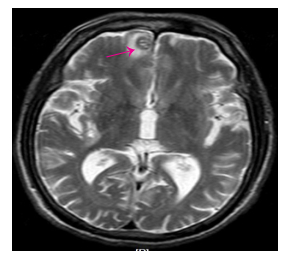

1 病例资料男,72岁,因反复上腹部疼痛、黑便、头晕4月于2016年6月17日收住我院消化内科,上腹部为阵发性胀痛,多能自行缓解,偶有呕吐,无呕吐咖啡样液或呕血,间歇性解黑便,每次量不大,头晕反复发作,无晕厥、黑朦、大汗淋漓、心悸。3 d前在外院查大便潜血阳性,患有高血压病2年余,规律服用降血压药物治疗,血压可控制。入院查体:中度贫血貌,心肺查体无异常,上腹部轻度膨隆,上腹部压痛,无反跳痛,未及腹部包块,肠鸣音活跃,6次/min,无气过水音。入院检查:白细胞10.86×109/L,血红蛋白76 g/L,红细胞压积0.25,血小板577×109/L,癌胚抗原21.78 ng/mL,大便潜血试验阳性。胃镜及结肠镜检查未见明显病变。胸片检查提示双下肺小许炎症。入院后禁食、质子泵抑制剂(PPI)抑酸护胃、止血、生长抑素、补液等治疗,上腹部胀痛无缓解,仍然间歇性有黑便解出。2016年6月24日查腹部CT提示(图 1、2):右上腹部空肠部分肠壁增厚、肠腔软组织密度肿块,考虑肿瘤病变;另左中腹部小肠局部肠壁增厚伴肠套叠改变,待排合并肿瘤,近段空肠轻度梗阻扩张。考虑小肠肿瘤并肠套叠、肠梗阻、小肠出血,遂于2016年6月25日行剖腹探查,术中见距离Treiz's韧带约50 cm处,空肠可扪及约5 cm大小肿物,质地硬,瘤体大部分位于小肠肠腔内,见肿瘤侵犯浆膜层;距离Treiz's韧带约60 cm处空肠见约5 cm肠管套叠,无法复位,其内可及约3 cm大小肿瘤,质地硬,考虑为肿瘤病变导致,空肠相关系膜内可见多发肿大淋巴结,最大直径约1.5 cm,质地韧,决定行空肠部分切除术:空肠切除约40 cm,近端肠管切缘约距离肿物约10 cm,远端肠管切缘约距离肠套叠病变约10 cm,包括扇形切除相应空肠系膜。术后病理显示(图 3):小肠肠管1段,长约35 cm,其中1段套叠,套叠长约6 cm,套叠内口直径约2 cm,外口直径约3 cm,肠管直径3~4.5 cm,距离一端切缘约10 cm处见溃疡型肿物,大小为5 cm×3 cm×0.7 cm,套叠肠管深处见1隆起型肿物,大小约为3.5 cm×3 cm×3 cm。光镜显示(图 4):异型细胞呈弥漫片状增生,局部呈巢团结构,细胞胞浆丰富,粉染,核大,圆形或不规则形,可见核仁,并可见大量瘤巨细胞,核分裂像多见。病理诊断:空肠肉瘤样癌,2个肿物,大小分别为5 cm×3 cm×0.7 cm、3.5 cm×3 cm×3 cm;侵犯肠壁全层;脉管见癌栓,未见神经侵犯,两端肠管切缘均未见癌累及;肠系膜淋巴结未见癌转移(0/29)。免疫组化:CK、CK19、Vimentin(+),CEA、CK20、Villin、CDX2、AFP、Hepatocyte(-),Ki-67约75%(+)。术后患者恢复顺利出院,拒绝行辅助化疗,密切随访,术后4月因精神异常返院复查,查颅脑MRI显示(图 5):双侧大脑半球及右侧小脑半球多发异常强化结节,考虑为转移瘤;脑萎缩。胸部CT显示(图 6):左肺上叶尖后段团块灶,伴空洞形成;右肺上叶后段肺门支气管-右肺门区肿块并右肺上叶阻塞性肺炎;双肺散在大小不等结节、团块灶;双肺肺气肿,多发肺大泡。纵隔内及双肺门区多发肿大淋巴结,部分伴坏死。腹部及盆腔CT增强扫描未发现明显肿物及肿大淋巴结等病变。考虑空肠肉瘤样癌术后肺、脑多发转移,术后8月因呼吸功能衰竭死亡。

图 5 脑转移病灶 Figure 5 Brain metastasis. |